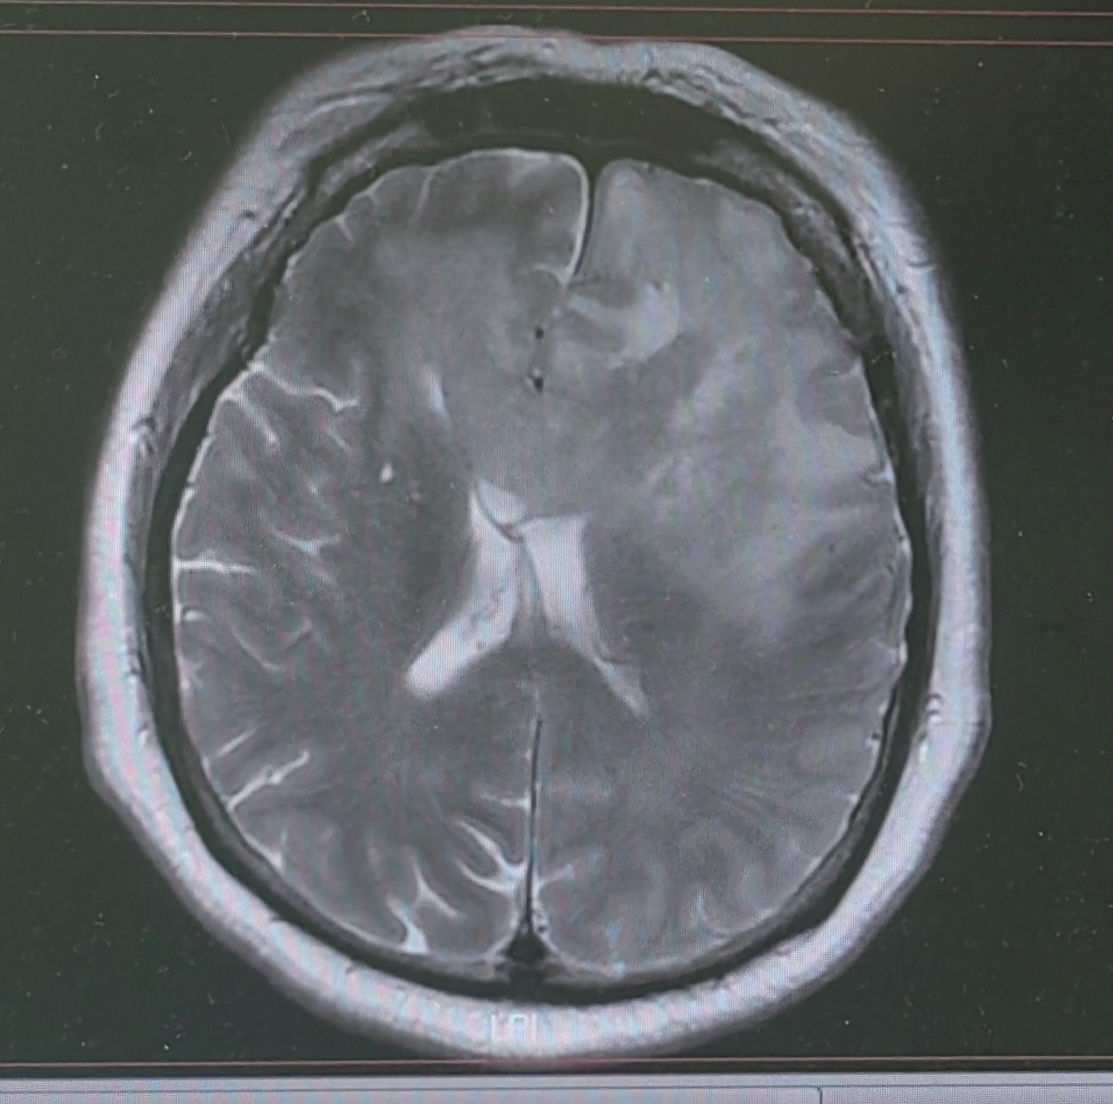

T2可见双侧额叶、胼胝体及左侧颞叶稍高信号病灶伴水肿